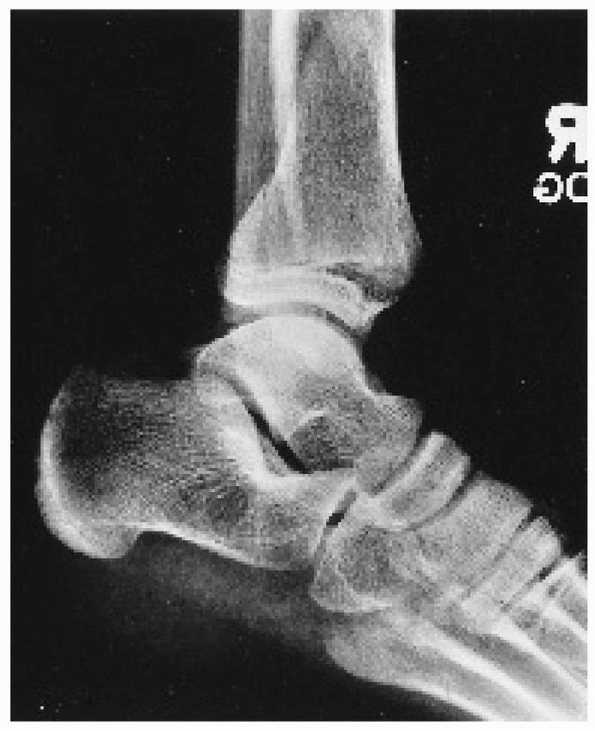

![]() |

FIGURE 26-9 A.

According to the Dias-Tachdjian classification, this injury in a 12-year-old boy would be considered a pronation-eversion-external rotation injury resulting in a Salter-Harris type II fracture of the distal tibia and a transverse fibular fracture. B. The anterior displacement of the epiphysis, visible on the lateral view, however, makes external rotation an unlikely component of the mechanism of injury; the mechanism is more likely pronation-dorsiflexion. |